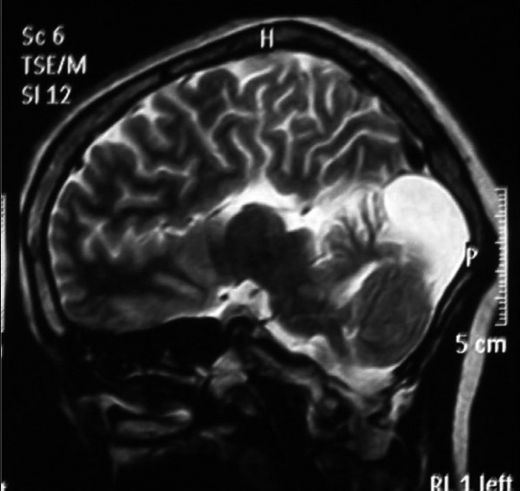

Dandy Walker sendromu, doğuştan gelen bir beyin anomalisidir ve genellikle beyincik ile ilgili yapısal bozuklukları ifade eder. Bu sendrom, beyincik kistleri, genişlemiş arka kafa bölgesi ve bazen de beyincik loblarının anormal gelişimi ile karakterizedir. Dandy Walker sendromu, çeşitli nörolojik ve fiziksel semptomlara yol açabilir. Dandy Walker Sendromunun BelirtileriDandy Walker sendromunun belirtileri bireyler arasında değişiklik gösterebilir. Ancak, en yaygın olarak görülen belirtiler şunlardır: